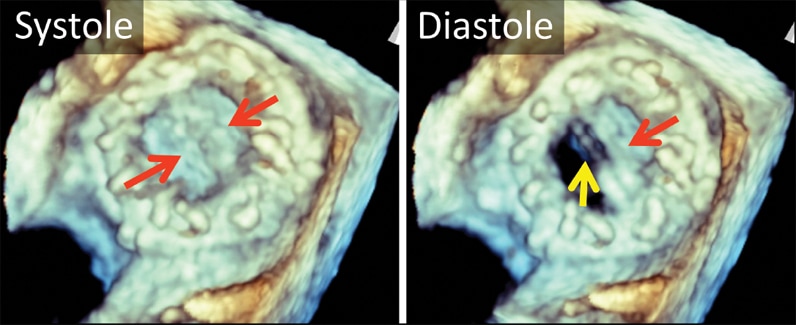

3-D transesophageal echocardiogram

3-D transesophageal echocardiogram

3-D transesophageal echocardiogram. Left atrial view of bileaflet mechanical mitral valve prosthesis. Note both leaflets in closed position in systole (left, arrows), with opening of only one disk in diastole (right, yellow arrow). The red arrow marks the fixed disk.